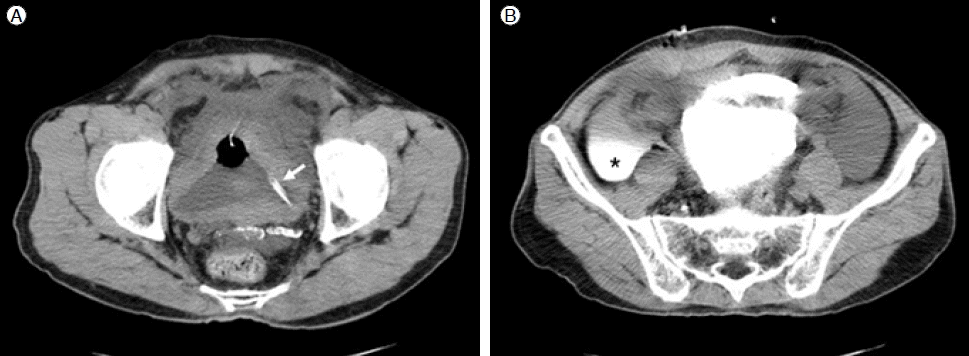

치료 및 경과: 수술 전 처치로 8시간 동안 금식을 하였으며 수술 직전 배뇨를 하였다. 수술은 국소 마취로 개복 없이 Tenckhoff 트로카를 사용하여 정중 절개법으로 시행하였다. 수술 후 환자가 자가 배뇨를 하지 못하여 도뇨관을 삽입하였다. 복강 내 세척을 위해 투석액 주입 및 배액을 반복하던 중 배액량이 적고, 도뇨관으로 투석액이 배액되는 것이 관찰되어 수술 중 방광 천자가 의심되었다. 방광 조영술을 병행한 컴퓨터 단층 촬영술(retrograde CT cystography)에서는 복막 투석 도관의 일부가 방광 내에 위치하고, 도뇨관을 통해 주입한 조영제가 복강 내로 유출되는 것을 확인하였다(Fig. 1). 이후 30분 뒤 재수술을 시행하여 방광 내로 삽입된 복막 도관을 제거하고, 도뇨관의 유지와 예방적 항생제 사용 등의 보존적 치료를 하였다. 소변량은 매일 1.5-2 L 정도로 유지되었고 발열이나 복통 등의 증상은 없었다. 일주일 후 신대치 요법을 위해 속목정맥 도관을 이용하여 혈액 투석을 시행하였다. 도뇨관 유치 후 14일째 역행성 방광 조영술을 실시하여(Fig. 2) 조영제의 유출이 없음과 방광 내벽의 무결성이 확인되어 도뇨관을 제거하였다. 이후 동정맥루 수술 후 퇴원하여 현재 주 3회 혈액 투석 시행 중이다.